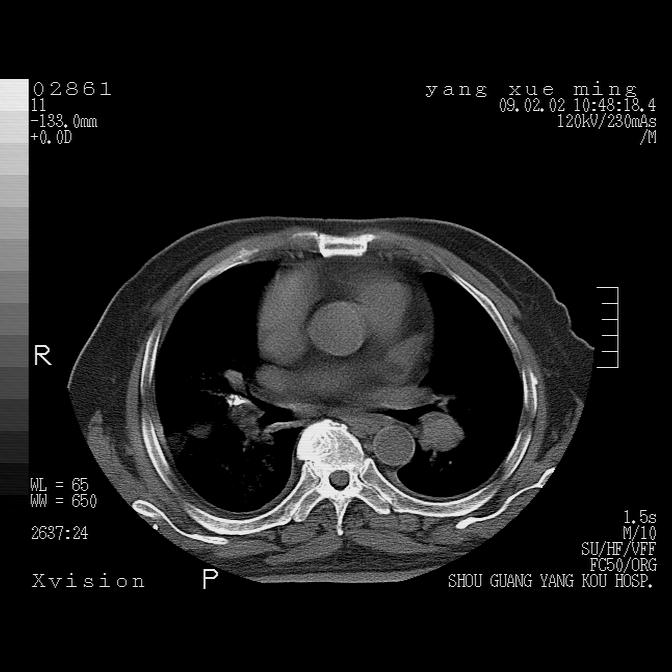

以下是引用zbp537在2009-2-3 19:08:00的发言:[br]我诊断为肺泡性肺水肿。[br]诊断依据:[br]1、心影普遍增大,肺血管增粗,并见絮状高密度影,肺门改变显著。[br]2、临床上表现胸闷咳嗽,无发烧,不是一个典型的肺部感染的病史。

以下是引用lkc8963在2009-2-3 20:11:00的发言:[br]1)右上肺陈旧病灶。2)右下肺团块及团片影,影像表现符合感染。3)左心增大,左冠脉钙化,符合冠心病。4)双侧肺门扩大,以左侧为著,肺动脉干略粗,左上肺局限性气肿,为谨慎起见,需除肿瘤,建议增强。

以下是引用lkc8963在2009-2-3 20:11:00的发言:[br]1)右上肺陈旧病灶.2)右下肺团块及团片影,影像表现符合感染.3)左心增大,左冠脉钙化,符合冠心病.4)双侧肺门扩大以左侧为著,肺动脉干略粗,左上肺局限性气肿,为谨慎起见,需除肿瘤,建议增强.